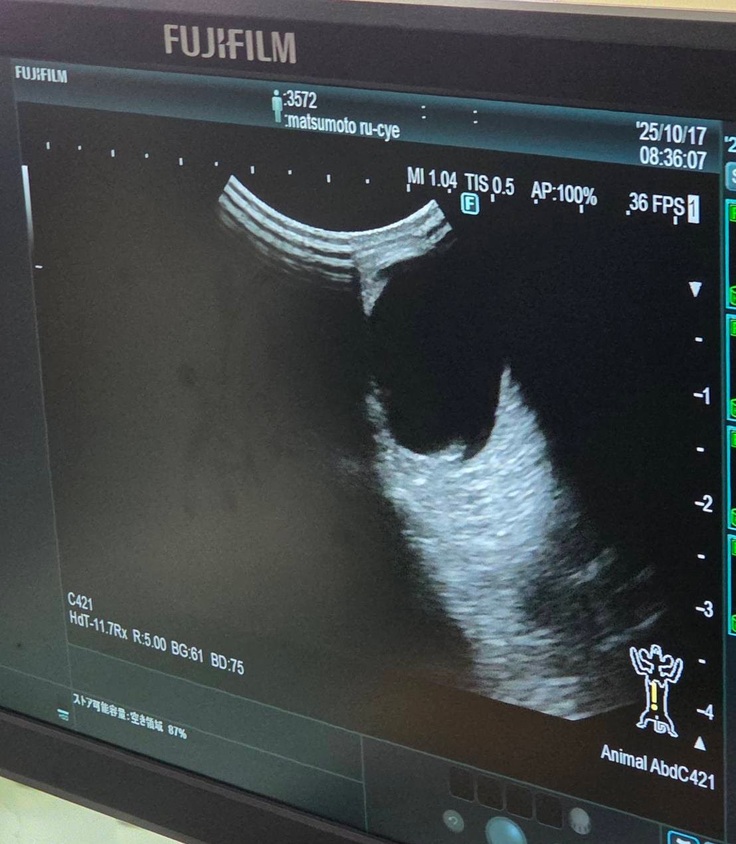

血液検査の写真は撮れなかったのですが、エコー検査では

↓腎臓転移なし

↓肝臓転移なし

↓膀胱転移なし

↓反対側の腎臓も転移なし

↓左目腫瘍なし

↓喉腫瘍なし

※正面から撮りたかったのですが先生がいたので撮れず、見づらくて申し訳ないです。